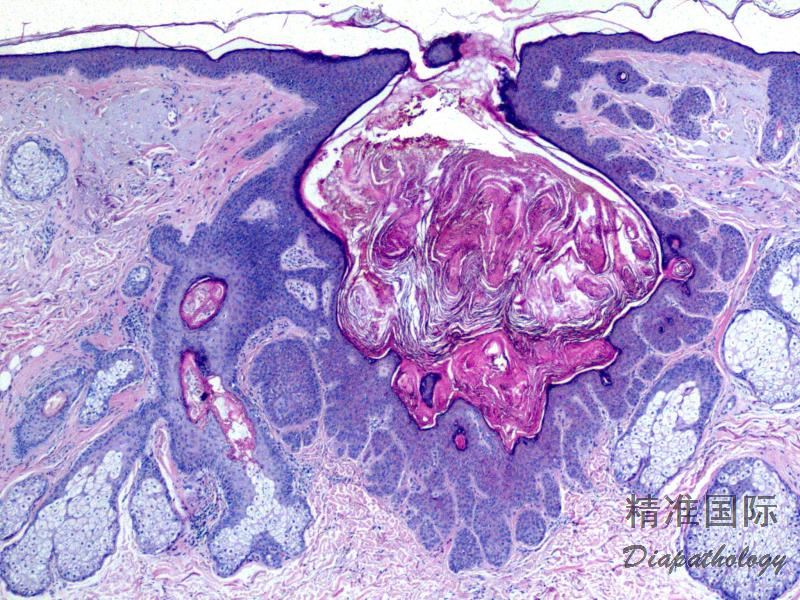

毛鞘棘皮瘤

Pilar Sheath Acanthoma

毛囊漏斗部明显扩大,呈不规则分支状囊腔,腔内充满角化物;

囊壁棘细胞向真皮和皮下组织增生,形成分叶状团块。